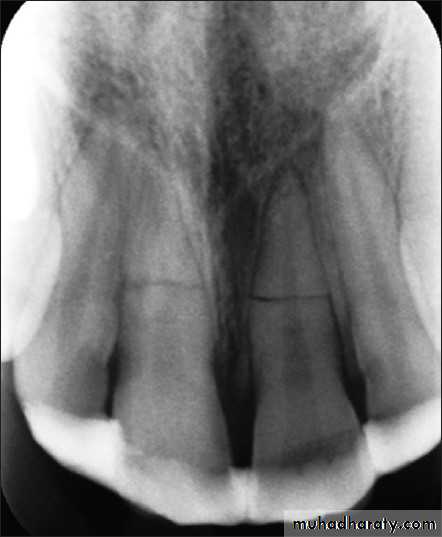

Pre-operative imaging

Conventional radiograph.

These two-dimensional (2D) images of three- dimensional (3D) structures have their limitations. For example, conventional periapical radiographs do not facilitate accurate predictions in the preoperative assessment for the potential perforation of the maxillary sinus. As a consequence the use of 3D cone-beam computed tomography (CBCT) imaging is now becoming established in preoperative assessment for PRS.